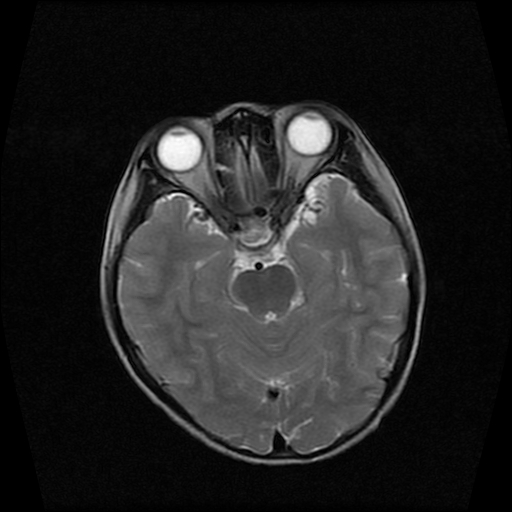

男性,12岁。反复头痛呕吐半月。脑积液无异常。病变部位ct值32hu,dwi无异常。

鞍上为主,累及鞍内,垂体受压位于鞍底。mri呈短t1、长t2信号,不太支持生殖细胞肿瘤,首考颅咽管瘤。

鞍内囊性占位性病变,t1wi、t2wi,均为高信号影。ct平扫为等密度。发病年龄较小。故首先考虑颅咽管瘤,可以做ct增强扫描